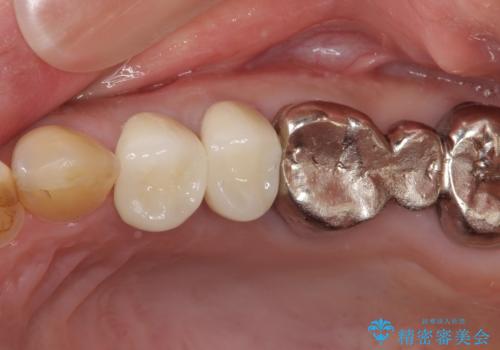

仮歯に変えた後にオールセラミッククラウンにて補綴することとしました。

治療前と比べてとても自然な前歯となり、患者様には大変満足していただきました。